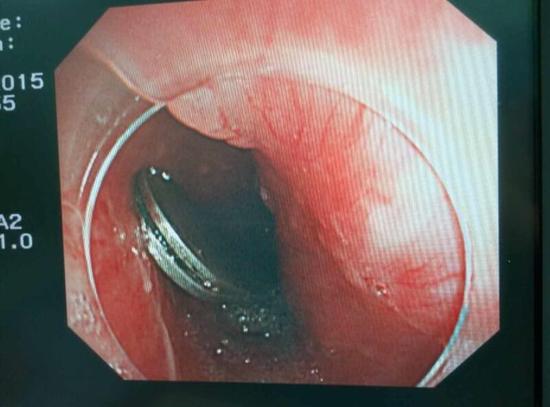

醫(yī)生從華先生胃里取出的鑷子和打火機

手術(shù)中,范醫(yī)生通過胃鏡準確發(fā)現(xiàn)了胃里的鑷子。但讓他驚訝的是,在華先生胃底竟然還躺著三個被腐蝕了的打火機,打火機的金屬部件都已經(jīng)不見了。

隨后,范醫(yī)生先用圈套器套取出了長10厘米的鑷子,再一個一個地取出了打火機。整個取出過程小心謹慎而又一氣呵成,只用了不到10分鐘。